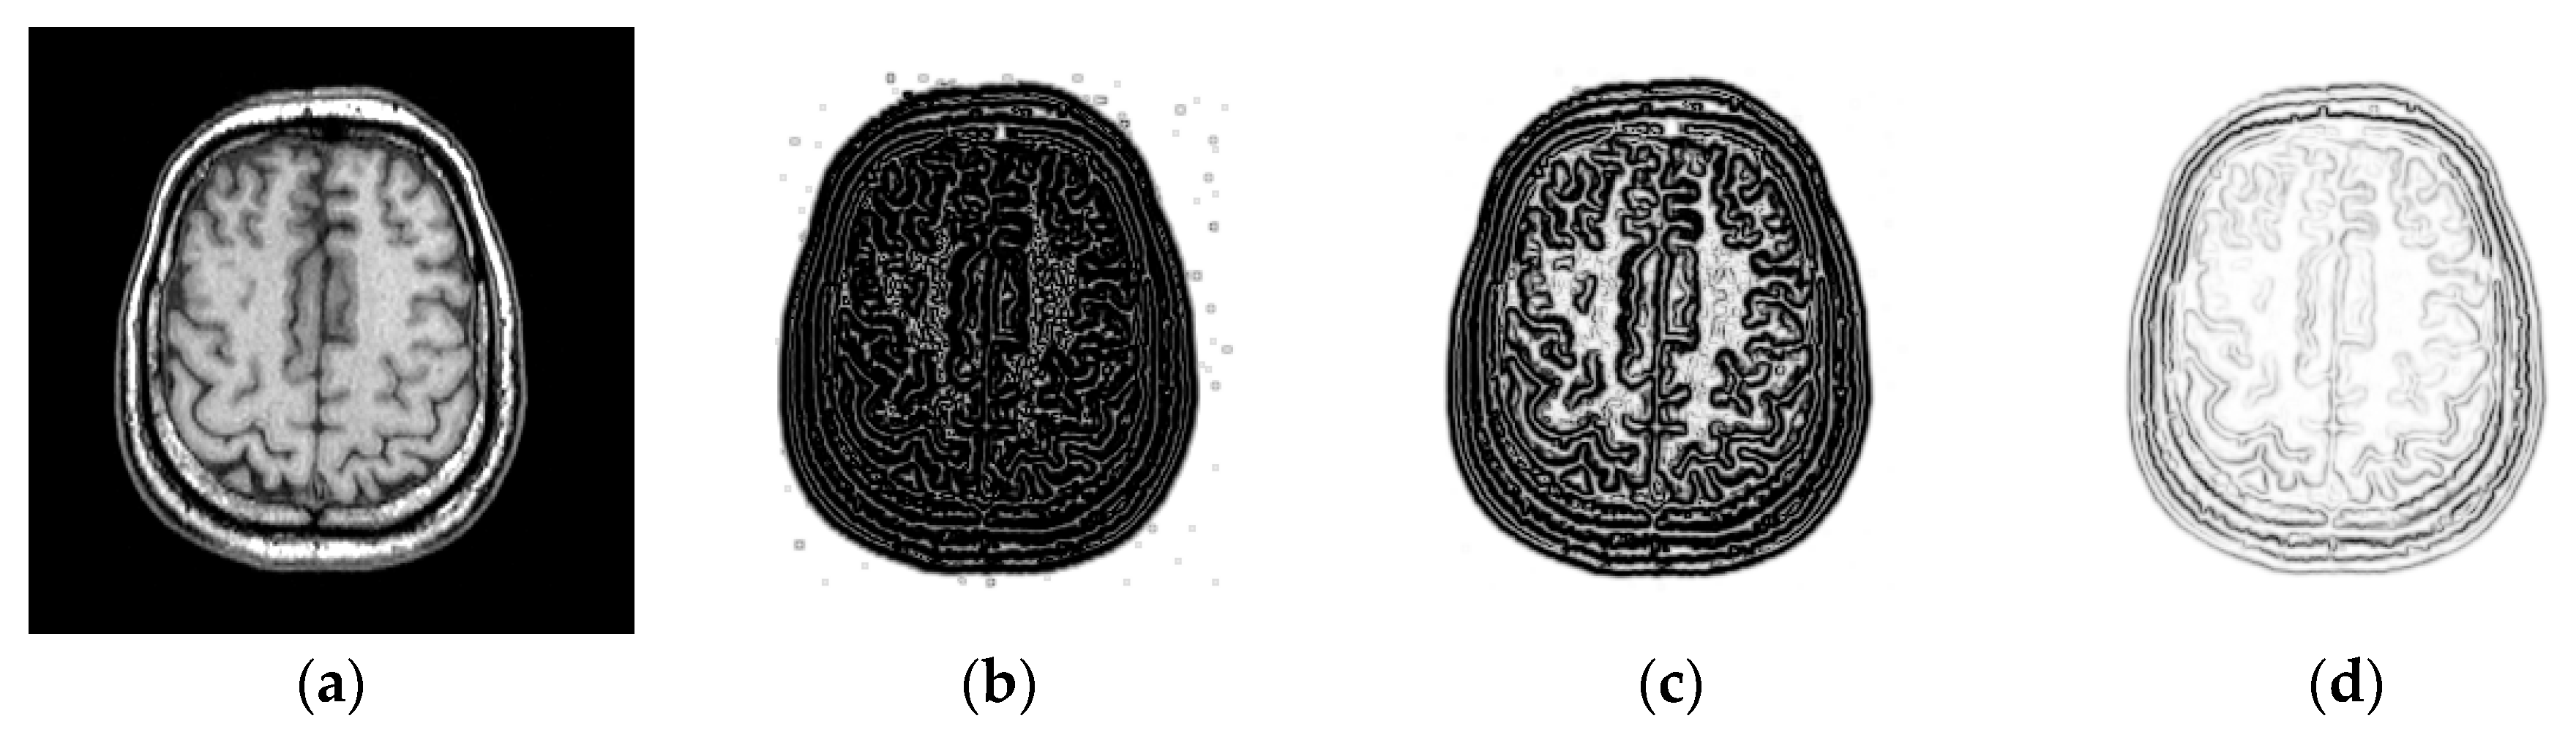

2.2. Structural Representation

3.1.1. Impact of the Patch Size